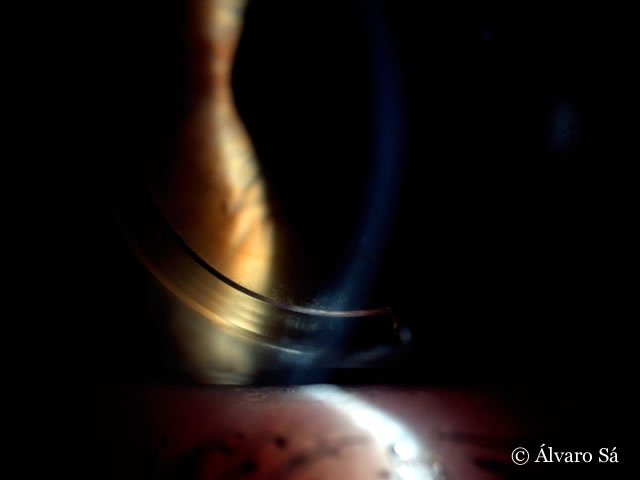

Fotografias do olho direito duas semanas após o implante do segmento de Anel.